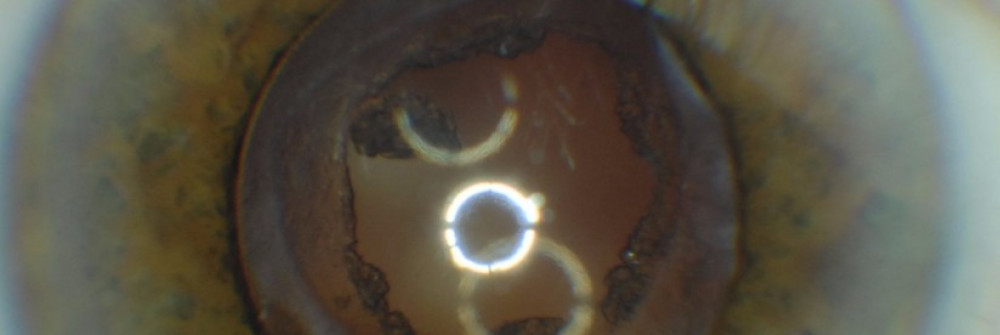

We provide Specialist Optometrist support for the YAG Laser clinics within the Trust, with a Specialist Optometrist working alongside the Ophthalmology team to assess and manage patients requiring YAG Laser treatment. The team carries out unilateral and bilateral posterior capsulotomies for patients who have developed posterior capsular opacification after cataract surgery and unilateral and bilateral peripheral iridotomies for patients at risk of angle closure glaucoma, with the YAG laser.